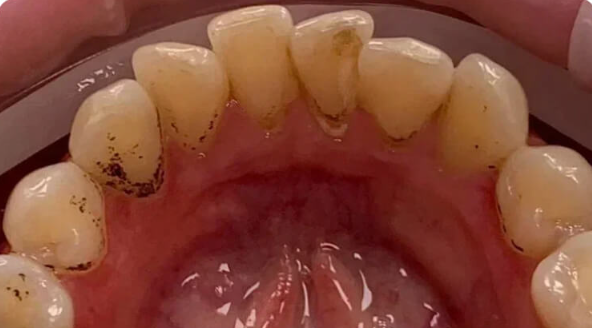

На странице представлено портфолио стоматологий Санкт-Петербурга с работами до и после профессиональной чистки зубов. В нашем портфолио собраны разные клинические случаи: от удаления незначительного налета до снятия массивного поддесневого камня. Здесь вы можете увидеть, как возвращается естественный цвет и внешний вид зубов после процедуры. Изучите результаты до и после чистки зубов, чтобы увидеть реальный эффект и выбрать клинику в Санкт-Петербурге, где профессиональная гигиена поможет вернуть зубам здоровый вид.

Профессиональная гигиена особенно важна при ортодонтическом лечении, ведь в повседневной жизни, дома, очень сложно поддерживать должный уровень гигиены полости рта! Даже если вы используете ирригатор и специальные ёршики! В нашей рубрике «до/после» вы видите то, что может быть с зубами при лечении брекетами, если не проводить своевременную чистку у врача-стоматолога. Марухно Дарья Александровна провела профессиональную чистку в несколько этапов, чтобы вернуть пациентке белизну ее собственных зубов! Брекет-система была поставлена не в нашей клинике, и почему пациентка не обратилась за профессиональной помощью раньше-вопрос) Но в данном случае, главное – итог! Кровоточивость после даже обычной чистки в такой клинической ситуации – естественный результат. Ведь обильный зубной налёт и зубной камень вызывают воспаление дёсен в виде гингивита, а порой даже пародонтита.

Доктор: Марухно Дарья Александровна